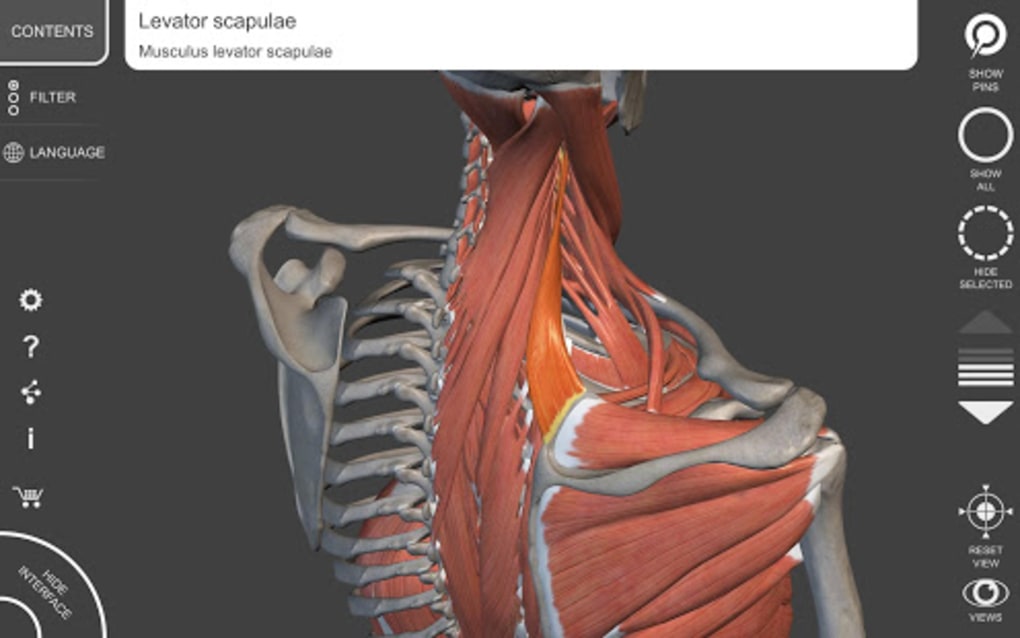

The app is based on the 3D model of the human body which is built with skeleton, muscles, bones, organs, and tissues. The anatomical models you will see in this app are the Respiratory System, Lymphatic system, Digestive System, Cardiovascular system, Eye and ear, and more.This app allows you to view the anatomy from a variety of angles, which makes it easy to study and understand.